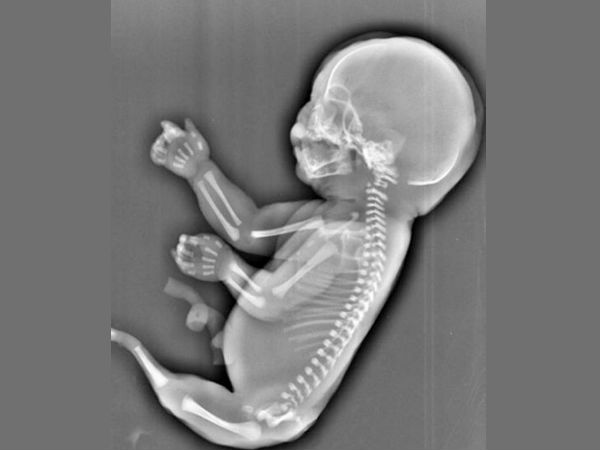

जानिए कब पहली बार गर्भ में भ्रूण का दिल धड़कता है?

जब अल्ट्रासाउंड के मॉनिटर पर बच्चे का दिल दिखाई देता है और धड़कनें चलती रहती हैं। लेकिन ऐसी बहुत सी चीजें हैं जिनकी आप कल्पना भी नहीं कर सकती।

आप बच्चे को जन्म देने वाली हैं! अधिकतर महिलाओं के लिए मातृत्व का ये एहसास पहली बार अल्ट्रा साउंड के साथ होता है।

भ्रूण की हार्टबीट, प्रिग्नेंसी, जन्म और बाद में भी आपके बच्चे के स्वास्थ्य में महत्वपूर्ण भूमिका निभाती है। ये अच्छी बात है कि आपके बच्चे की दिल की धड़कनों को देखने की तकनीक कई जानकारियाँ प्रदान करती है, गर्भावस्था के दौरान सब ठीक रहे और जन्मजात दिल की बीमारियों का जल्दी ही पता चल जाता है।

बच्चे का हार्ट –

शुरुआत में एक ट्यूब की संरचना का होता है जो कि एक चेम्बर्ड अंग में विकसित होता है जिससे हम वाकिफ हैं, निषेचन के कुछ दिनों बाद ही यह विकसित हो जाता है। हम इस बारे में आपको कुछ जानकारी प्रदान कर रहे हैं।

तीसरा सप्ताह: निषेचन के 22 दिन बाद भ्रूण का दिल बनना शुरू होता है, लेकिन इसकी धड़कनें सुनाई नहीं देती हैं।

पांचवा सप्ताह : भ्रूण का हार्ट चेम्बर विकसित होना शुरू होता है।

छठा सप्ताह: हार्ट रेट 100-160 बीट्स पर मिनट (बीपीएम) हो जाती है। इस समय आप अल्ट्रासाउंड मॉनिटर पर धड़कनें देख सकते हैं।

आठवा सप्ताह: बच्चे की हार्टबीट में एक स्थिर रिदम होती है।

दसवां सप्ताह: हार्ट रेट 170 बीपीएम तक बढ़ जाती है और जन्म के समय 130 बीपीएम के लगभग स्थिर हो जाती है।